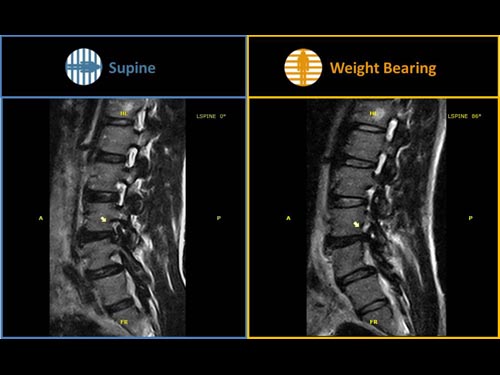

Nová končetinová magnetická rezonance G-scan Brio od společnosti Esaote je tomografický systém MRI, který umožňuje studium všech kloubů i páteře, ať už v klinostatické (vleže) nebo ortostatické (vážící) poloze, protože magnet i pacient se mohou otáčet od 0 do 90 stupňů. Díky inovativnímu designu G-scan mohou být pacienti Brio skenováni v poloze nesoucí váhu, aby se usnadnila diagnostika MSK u těch patologií, které se mohou měnit v důsledku držení těla a polohy, jako jsou bolesti dolní části zad.

• Váhové ložisko: poloha pacienta se stává nedílnou součástí výsledku vyšetření

• Další diagnostické schopnosti: jelikož gravitační síla generuje bio-mechanické změny v anatomii, MR zobrazení v přirozené poloze ve stoje vám umožňuje dosáhnout důležitých dalších informací ve srovnání s tradičními MRI

G-scan Brio je speciálně navržen pro všechny aplikace pohybového aparátu. Otevřený a naklápěcí design je nový a inovativní způsob provádění MRI, při kterém se poloha pacienta stává nedílnou součástí výsledku vyšetření. G-scan Brio poskytuje pacientovi vysoký komfort s funkcí nejnovějšího zobrazovacího výkonu a sekvencí společnosti Esaote.